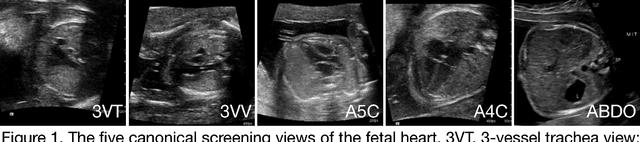

Abstract:Prenatal diagnosis of tetralogy of Fallot (TOF) and hypoplastic left heart syndrome (HLHS), two serious congenital heart defects, improves outcomes and can in some cases facilitate in utero interventions. In practice, however, the fetal diagnosis rate for these lesions is only 30-50 percent in community settings. Improving fetal diagnosis of congenital heart disease is therefore critical. Deep learning is a cutting-edge machine learning technique for finding patterns in images but has not yet been applied to prenatal diagnosis of congenital heart disease. Using 685 retrospectively collected echocardiograms from fetuses 18-24 weeks of gestational age from 2000-2018, we trained convolutional and fully-convolutional deep learning models in a supervised manner to (i) identify the five canonical screening views of the fetal heart and (ii) segment cardiac structures to calculate fetal cardiac biometrics. We then trained models to distinguish by view between normal hearts, TOF, and HLHS. In a holdout test set of images, F-score for identification of the five most important fetal cardiac views was 0.95. Binary classification of unannotated cardiac views of normal heart vs. TOF reached an overall sensitivity of 75% and a specificity of 76%, while normal vs. HLHS reached a sensitivity of 100% and specificity of 90%, both well above average diagnostic rates for these lesions. Furthermore, segmentation-based measurements for cardiothoracic ratio (CTR), cardiac axis (CA), and ventricular fractional area change (FAC) were compatible with clinically measured metrics for normal, TOF, and HLHS hearts. Thus, using guideline-recommended imaging, deep learning models can significantly improve detection of fetal congenital heart disease compared to the common standard of care.